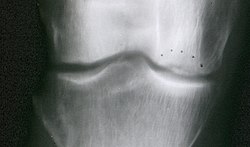

Der Morbus Ahlbäck ist eine akute Nekrose (Gewebsuntergang) im druckbelasteten Teil des Oberschenkelknochens am Kniegelenk.

Er zählt zu den aseptischen (nicht durch eine Infektion verursachten) Osteonekrosen. Er findet sich meist an der inneren (medialen) Kondyle (Knochenrolle) des kniegelenkbildenden Anteils des Oberschenkelknochens. Als Ursache werden Durchblutungsstörungen der versorgenden Arterien vermutet; eventuell auch mechanische Überlastung. Betroffen sind überwiegend Frauen jenseits des 60. Lebensjahres. Die Erkrankung ist häufiger bei Personen mit Stoffwechselerkrankungen, Diabetes, Alkoholismus, unter Chemotherapie, oder nach langdauernder Steroidbehandlung.[1]

Die Einteilung in Stadien I-IV nach Koshino richtet sich nach der Bildgebung (St. I = nur im MR und Szintigramm sichtbar; St. II = leichte Aufhellungslinie im Röntgenbild; St. III = deutlich im Röntgenbild sichtbar, St. IV = eingebrochen und deformiert).

Im Frühstadium zeigt sich im Röntgenbild die Osteolyse durch eine Aufhellung der Knochensubstanz. Nicht in allen Fällen ist die Osteolyse umgeben von einem Sklerosesaum. Mit Hilfe der Computertomographie kann das genaue Ausmaß der Zerstörung des Knochens auch schon in frühen Stadien dargestellt werden. Die Knochenszintigraphie zeigt manchmal eine Nuklidanreicherung in der Umgebung des abgestorbenen Knochenstücks.

| Nekrose des medialen Femurkondylus (M. Ahlbäck) bei einer 68-jährigen Frau | eigenes Archiv | Mehlauge | Datei:M. Ahlbäck.JPG | |